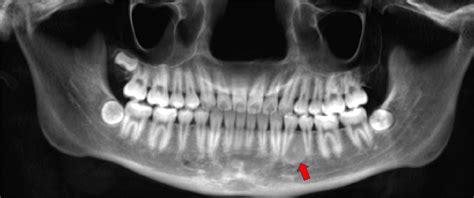

When you visit a dentist, they will perform a thorough clinical examination. Because many different types of oral lesions can look similar, your dentist will assess the site of the lesion relative to your teeth and appliances. If the lesion is located exactly where a sharp tooth edge or a denture border contacts the tissue, the diagnosis of an irritation fibroma becomes highly probable.

In most cases, a clinical diagnosis is sufficient. However, if the lesion appears atypical, grows rapidly, or has an unusual appearance, the dentist may recommend an excisional biopsy. This is a simple procedure where the tissue is removed and sent to a laboratory to be examined under a microscope by a pathologist. This is a standard precautionary measure to ensure the lesion is indeed benign.